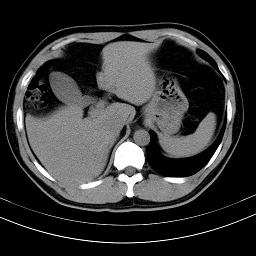

标题: CT18388:肝脏膈肌间隙内大量脂肪密度影 [打印本页]

标题: CT18388:肝脏膈肌间隙内大量脂肪密度影

是脂肪不是气体,有时候会碰到这样的病人,脂肪过多吧。

腹腔脂肪沉积过多

膈下脂肪沉积。

考虑膈下脂肪沉积。

激素治疗的病人容易脂肪沉积